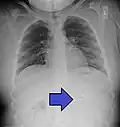

Foreign material in a blood vessel due to an embolization procedure.